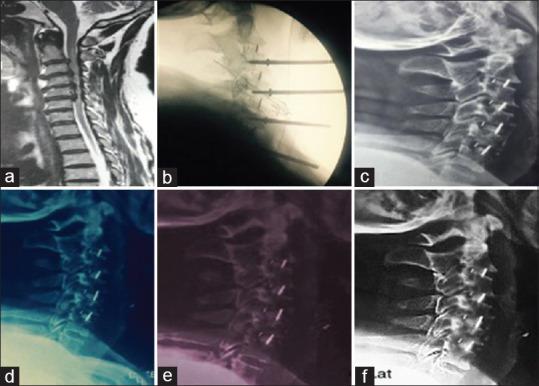

用于连续四个节段退行性椎间盘疾病的前路颈椎间盘切除融合术的独立聚醚醚酮椎间融合器,无需钢板固定。

Stand-alone polyetheretherketone cages for anterior cervical discectomy and fusion for successive four-level degenerative disc disease without plate fixation.

The aim of this study is to evaluate the safety and efficacy of the stand-alone cervical polyetheretherketone (PEEK) cages in four-level discectomy and to determine if it is possible to avoid anterior plate fixation and to achieve satisfactory outcomes.

METHODOLOGY

This is a retrospective study which was performed between June 2011 and December 2018 at one institute. The clinical and radiological data were collected from patients who underwent successive four-level anterior cervical discectomy and fusion with PEEK cages for degenerative cervical disc disease without plate fixation.

RESULTS

This study included 66 patients, 35 males and 31 females. The follow-up period was 24 months. Mean Japanese Orthopedic Association scores were 13.3 ± 1.41 preoperative and 15.9 ± 0.86 postoperative ( = 0.046). The cervical curvature index "Ishihara" (ICI) was 9.9 ± 5.90 preoperative and the mean of ICI was 10.5 ± 6.65 postoperative, which is insignificant, = 0.7). The lordotic curvature according to these results was preserved till the end of the year and half of the follow-up period postoperative.

CONCLUSION

Consecutive four-level anterior discectomy with PEEK cage interbody fusion without plate and screw is a safe and effective procedure in the absence of instability, and it may be a reliable alternative for the treatment of multilevel cervical disc.

本研究的目的是评估独立颈椎聚醚醚酮(PEEK)椎间融合器在四级椎间盘切除术中的安全性和有效性,并确定是否有可能避免前路钢板固定并取得满意的结果。

方法

这是一项回顾性研究,于2011年6月至2018年12月在一家机构进行。收集了因退行性颈椎间盘疾病接受连续四级颈椎前路椎间盘切除并使用PEEK椎间融合器融合且未进行钢板固定的患者的临床和放射学数据。

结果

本研究纳入66例患者,其中男性35例,女性31例。随访期为24个月。术前日本骨科协会平均评分为13.3±1.41,术后为15.9±0.86(P = 0.046)。颈椎曲度指数“Ishihara”(ICI)术前为9.9±5.90,术后ICI平均值为10.5±6.65,差异无统计学意义(P = 0.7)。根据这些结果,前凸曲度在术后随访期的一年半内得以保留。

结论

在不存在不稳定的情况下,连续四级颈椎前路椎间盘切除并使用PEEK椎间融合器进行椎间融合而不使用钢板和螺钉是一种安全有效的手术方法,可能是治疗多节段颈椎间盘疾病的可靠替代方法。